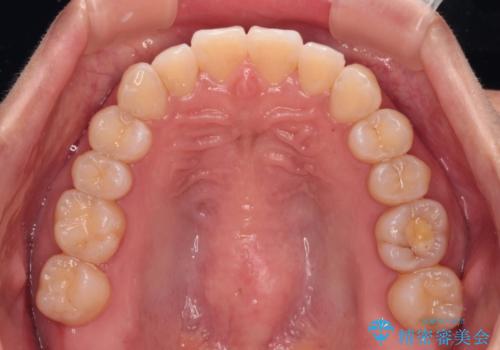

上顎前歯が捻れて前方に飛び出しており、下顎前歯もそれに沿うようにデコボコとなっていました。

IPR(歯と歯の間を削る処置)によりスペースを獲得して上下顎前歯のデコボコを改善し、飛び出している前歯が引っ込むように設定し、インビザラインにて矯正治療を行うこととしました。